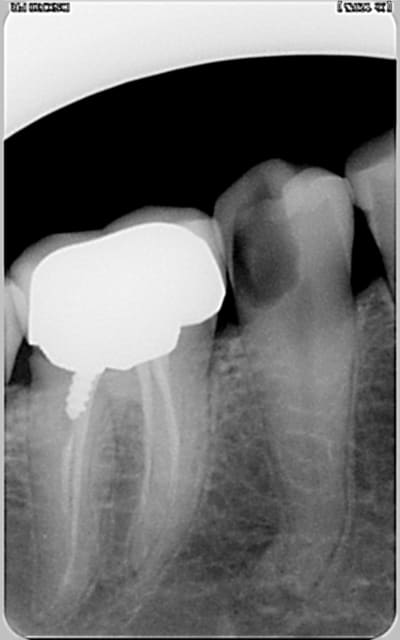

encore des radios,peut-etre assez moyen comme traitement...mais je vu pire...

les dernieres radios. patient en urgence ,abces... il voulait pas extraire la dent. j'ai lui bien explque et il a choisi de essayer de garder la dent. retrait,pas d'isolation avec la digue donc pas de tenon fibree,amalgam et screw post.traitement fait il ya 2 ans je crois.patient fidel de cabinet maintenent.

j'ai jamais utilise en roumanie l'amalgam et ca s'utilise pas du tout dans le cabinet du roumanie.